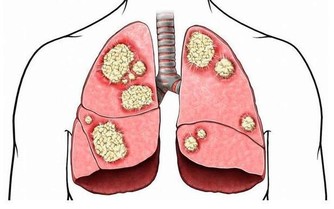

在新型肺炎的高危時期,禽流感又​​捲土重來了,讓大家的惶恐又加重了許多!

實際上,大家除了少出門,勤洗手,多通風,出門戴口罩之外,提高自己身體的免疫力也是抵禦病毒的有效方法之一。

要知道,一旦我們人體的免疫力下降,各種疾病就都有了可乘之機。有專家指出,在日常生活中做好以下幾點,增強身體免疫力——